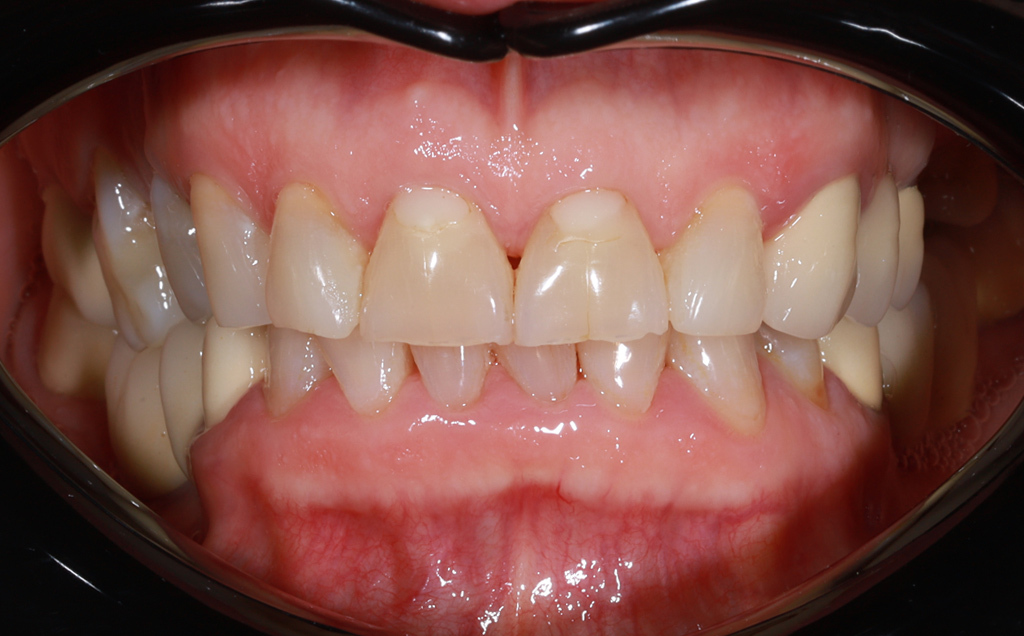

Zaprezentujemy serię poruszających historii pacjentów, którzy zdecydowali się na kompleksowe leczenie dentystyczne. Od przypadków zaawansowanej próchnicy, przez wypadki, które wymagały rekonstrukcji zębów, po pacjentów marzących o hollywoodzkim uśmiechu dzięki zastosowaniu licówek – każda historia jest dowodem na to, jak nowoczesna stomatologia może odmienić życie.

Pełna higienizacja: usunięcie kamienia i osadu (scaling, piaskowanie).

Metamorfoza uśmiechu: usunięcie przebarwień i kamienia nazębnego.